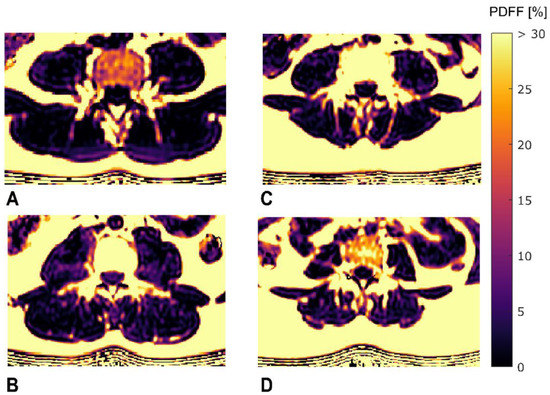

2.2. MR Imaging

2.3. MR Image Segmentation

2.4. Texture Analysis of PDFF Maps